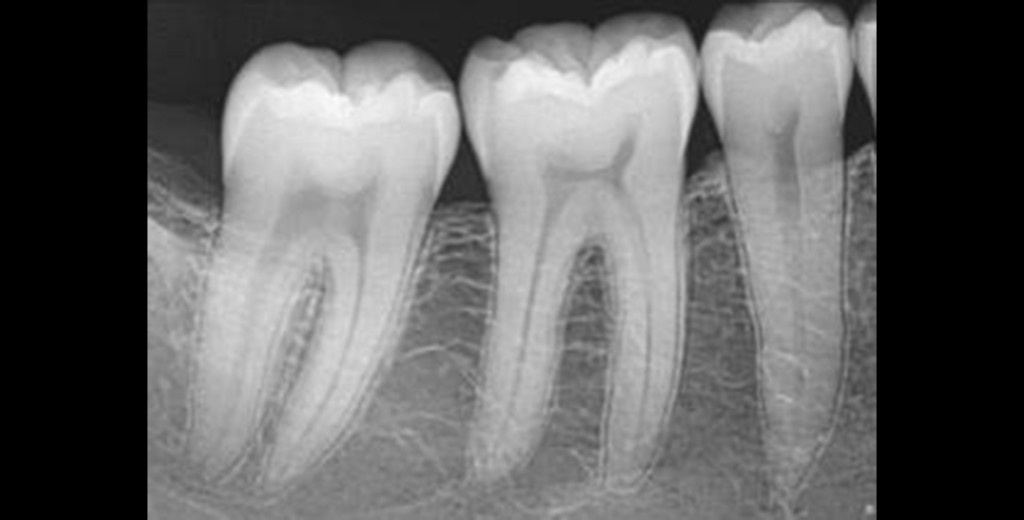

RADIOGRAFÍA

PERIAPICALES INDIVIDUAL

Desde el diagnóstico hasta el seguimiento postoperatorio, es tu aliada silenciosa en cada paso.